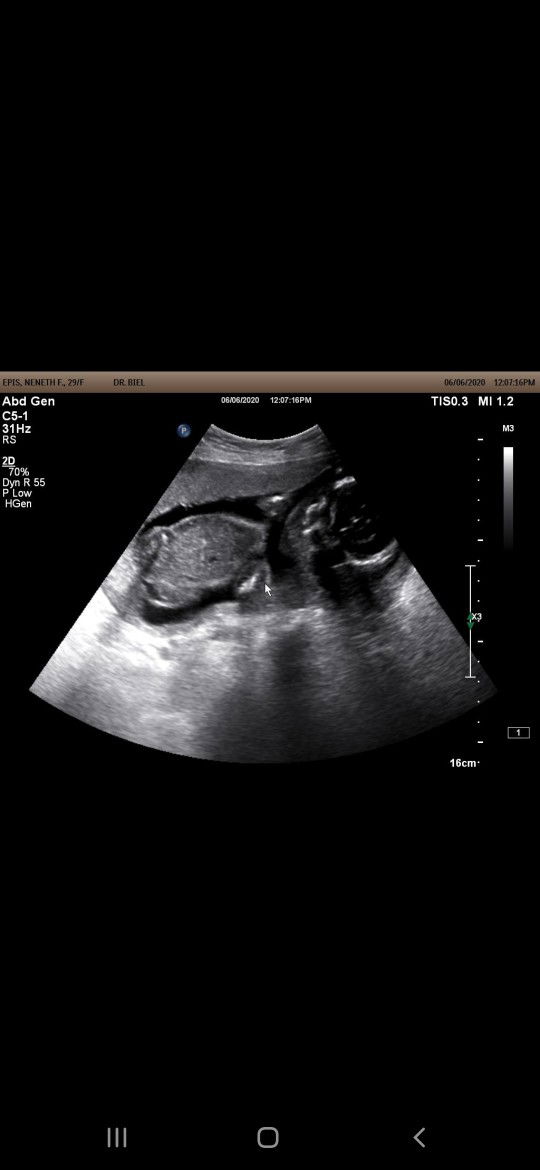

Hi ano po reason bakit sumasakit boobs ko πͺ 21 weeks preggy po. Thanks

Hi ano po reason bakit sumasakit boobs ko πͺ 21 weeks preggy po. Thanks #FTM